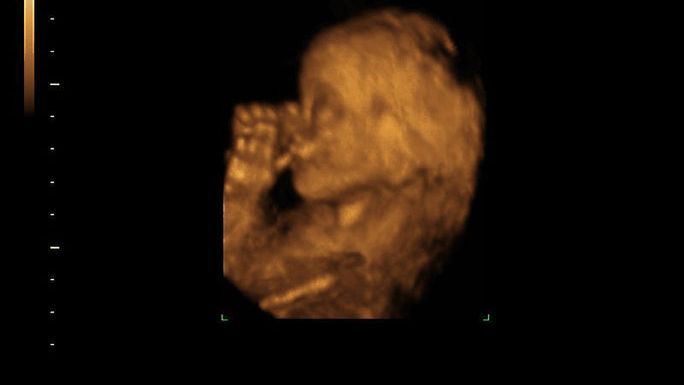

Źródło zdjęć: © Thinkstockphotos